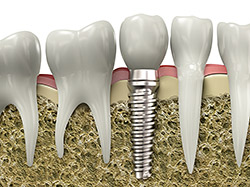

If you are missing teeth, it is crucial to replace them. Without all your teeth, chewing and eating can destabilize your bite and cause you discomfort. When teeth are missing, your mouth can shift and even cause your face to look older. Implants are a great way to replace your missing teeth, and if properly maintained, can last a lifetime!

An implant is a new tooth made of metal and porcelain that looks just like your natural tooth. It’s composed of two main parts: One is the titanium implant body that takes the place of the missing root, and the other is the tooth-colored crown that is cemented on top of the implant. With implant treatment, you can smile confidently, knowing no one will ever suspect you have a replacement tooth.

In addition to tooth replacement, implants may be used to anchor dentures, especially lower dentures that tend to shift when you talk or chew. For patients with removable partial dentures, implants can replace missing teeth so you have a more natural-looking smile.